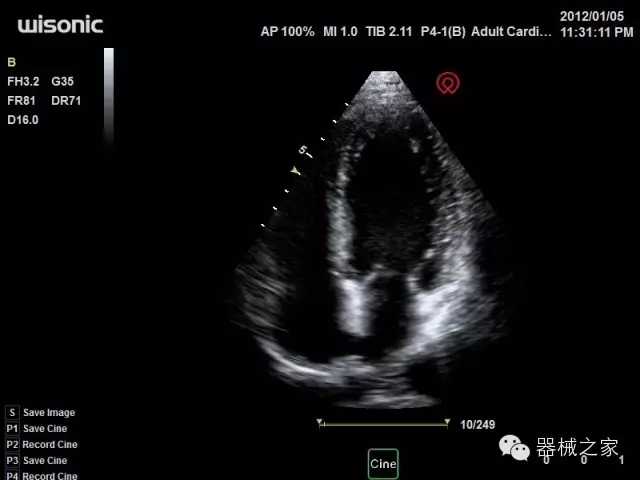

臨床圖片賞析

產(chǎn)品特點

·全球目前唯一一款配備主機(jī)雙探頭接口,整機(jī)重量(含電池)在5公斤以內(nèi)的便攜式彩超;

·一款互聯(lián)網(wǎng)彩超,只要有手機(jī)信號的地方就可以非常方便地實現(xiàn)遠(yuǎn)程會診和病案調(diào)??;